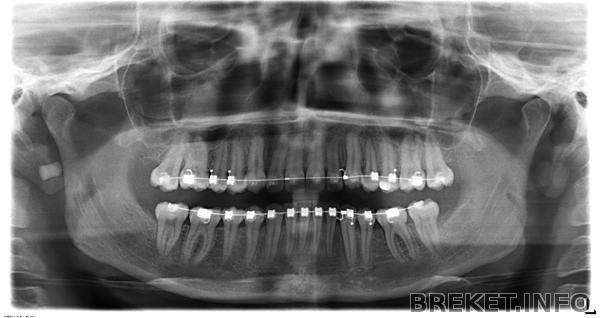

прошло 2 года 6 месяцев, фух, неужели дожила?!

Соответственно, двадцать четыре месяца - НЧ

Цель № 2 - наиболее важная часть - делить существование с БС не больше шести месяцев

Ибо это мой предел